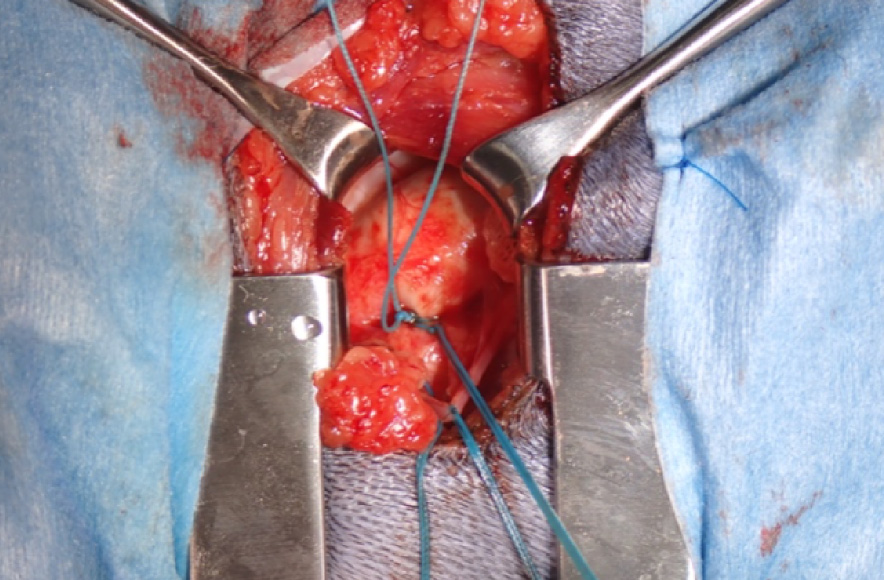

手術前

| 犬種 | マルチーズ 11歳 5kg |

| 治療と経過 | 術後には僧帽弁の逆流が大幅に減少あるいは消失することで、心臓への負担が軽減され術前と比較して心臓サイズが縮小します。多くの症例で術後1ヵ月以内に今まで飲んでいた循環器系の内服薬が不要となります。術後3ヵ月までは、術後血栓症のリスクがあるため抗血栓治療が必要となります。 |